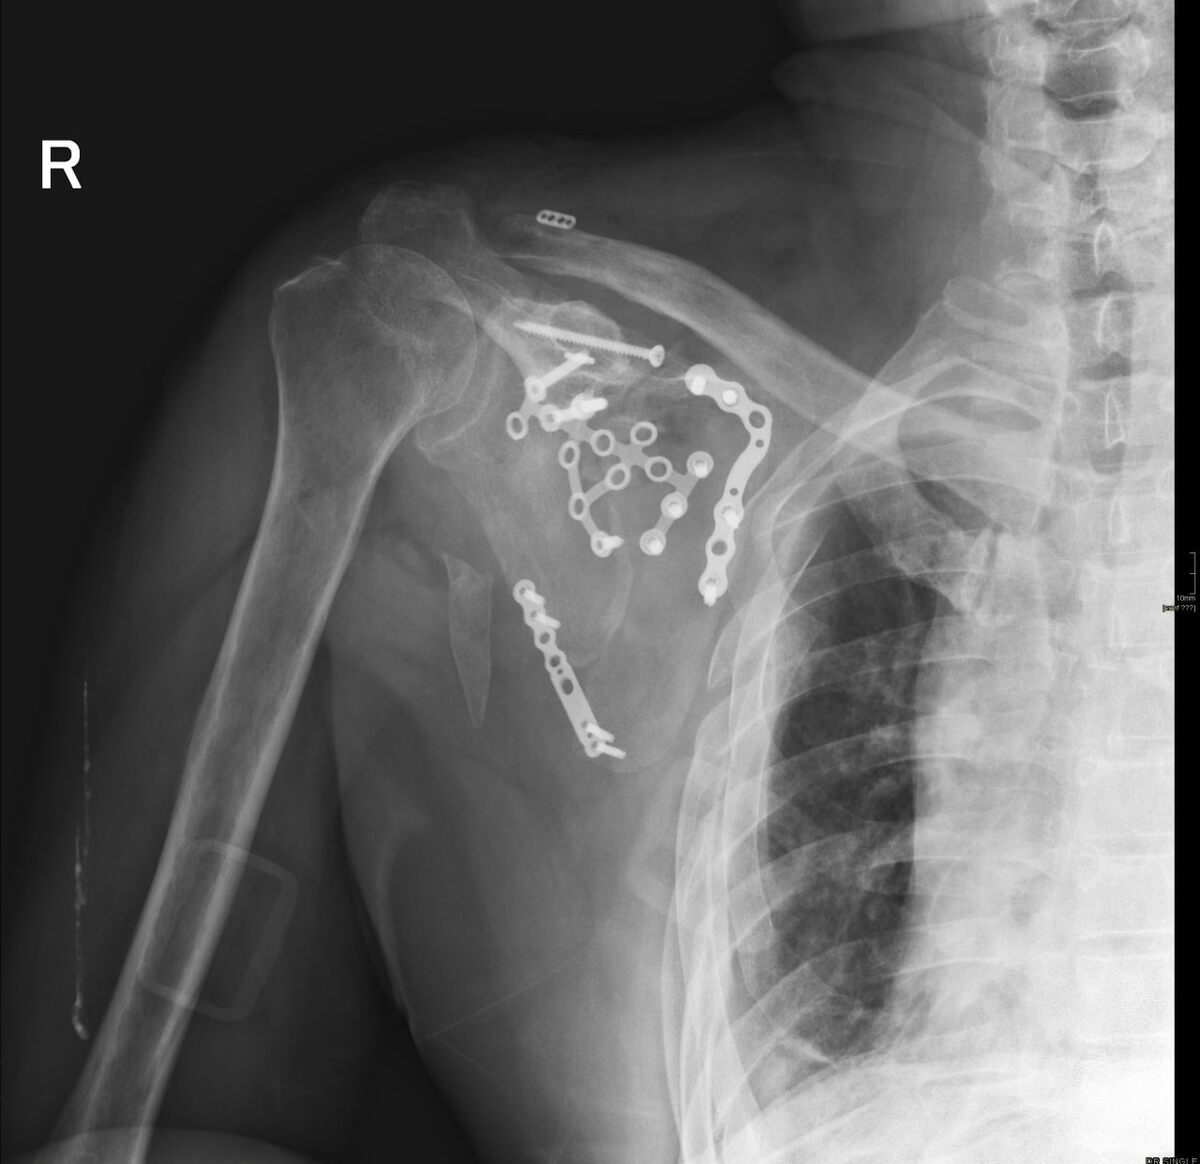

Тогда пациент по совету обратился в Университетскую клинику РУДН. Наша квалифицированная команда врачей травматологического отделения по результатам обследования выявила осложненный перелом лопатки, разрыв связок ключично-акромиального сочленения с вывихом ключицы, необходимо было проведение оперативного лечения.

⚪️Сначала мы восстановили форму лопатки, установили костные трансплантаты и зафиксировала всё пластиной. Затем выполнили доступ к акромиально-ключичному суставу, который был вправлен и зафиксирован сухожильным трансплантатом, взятым из области голеностопного сустава. Для удержания трансплантатов использовались специальные медицинские "пуговицы" - металлические пластины, которые синтетической лентой надежно крепятся к кости⚪️, - прокомментировал заведующий травматологическим отделением, врач - травматолог-ортопед Кирилл Васильевич Сидорук.